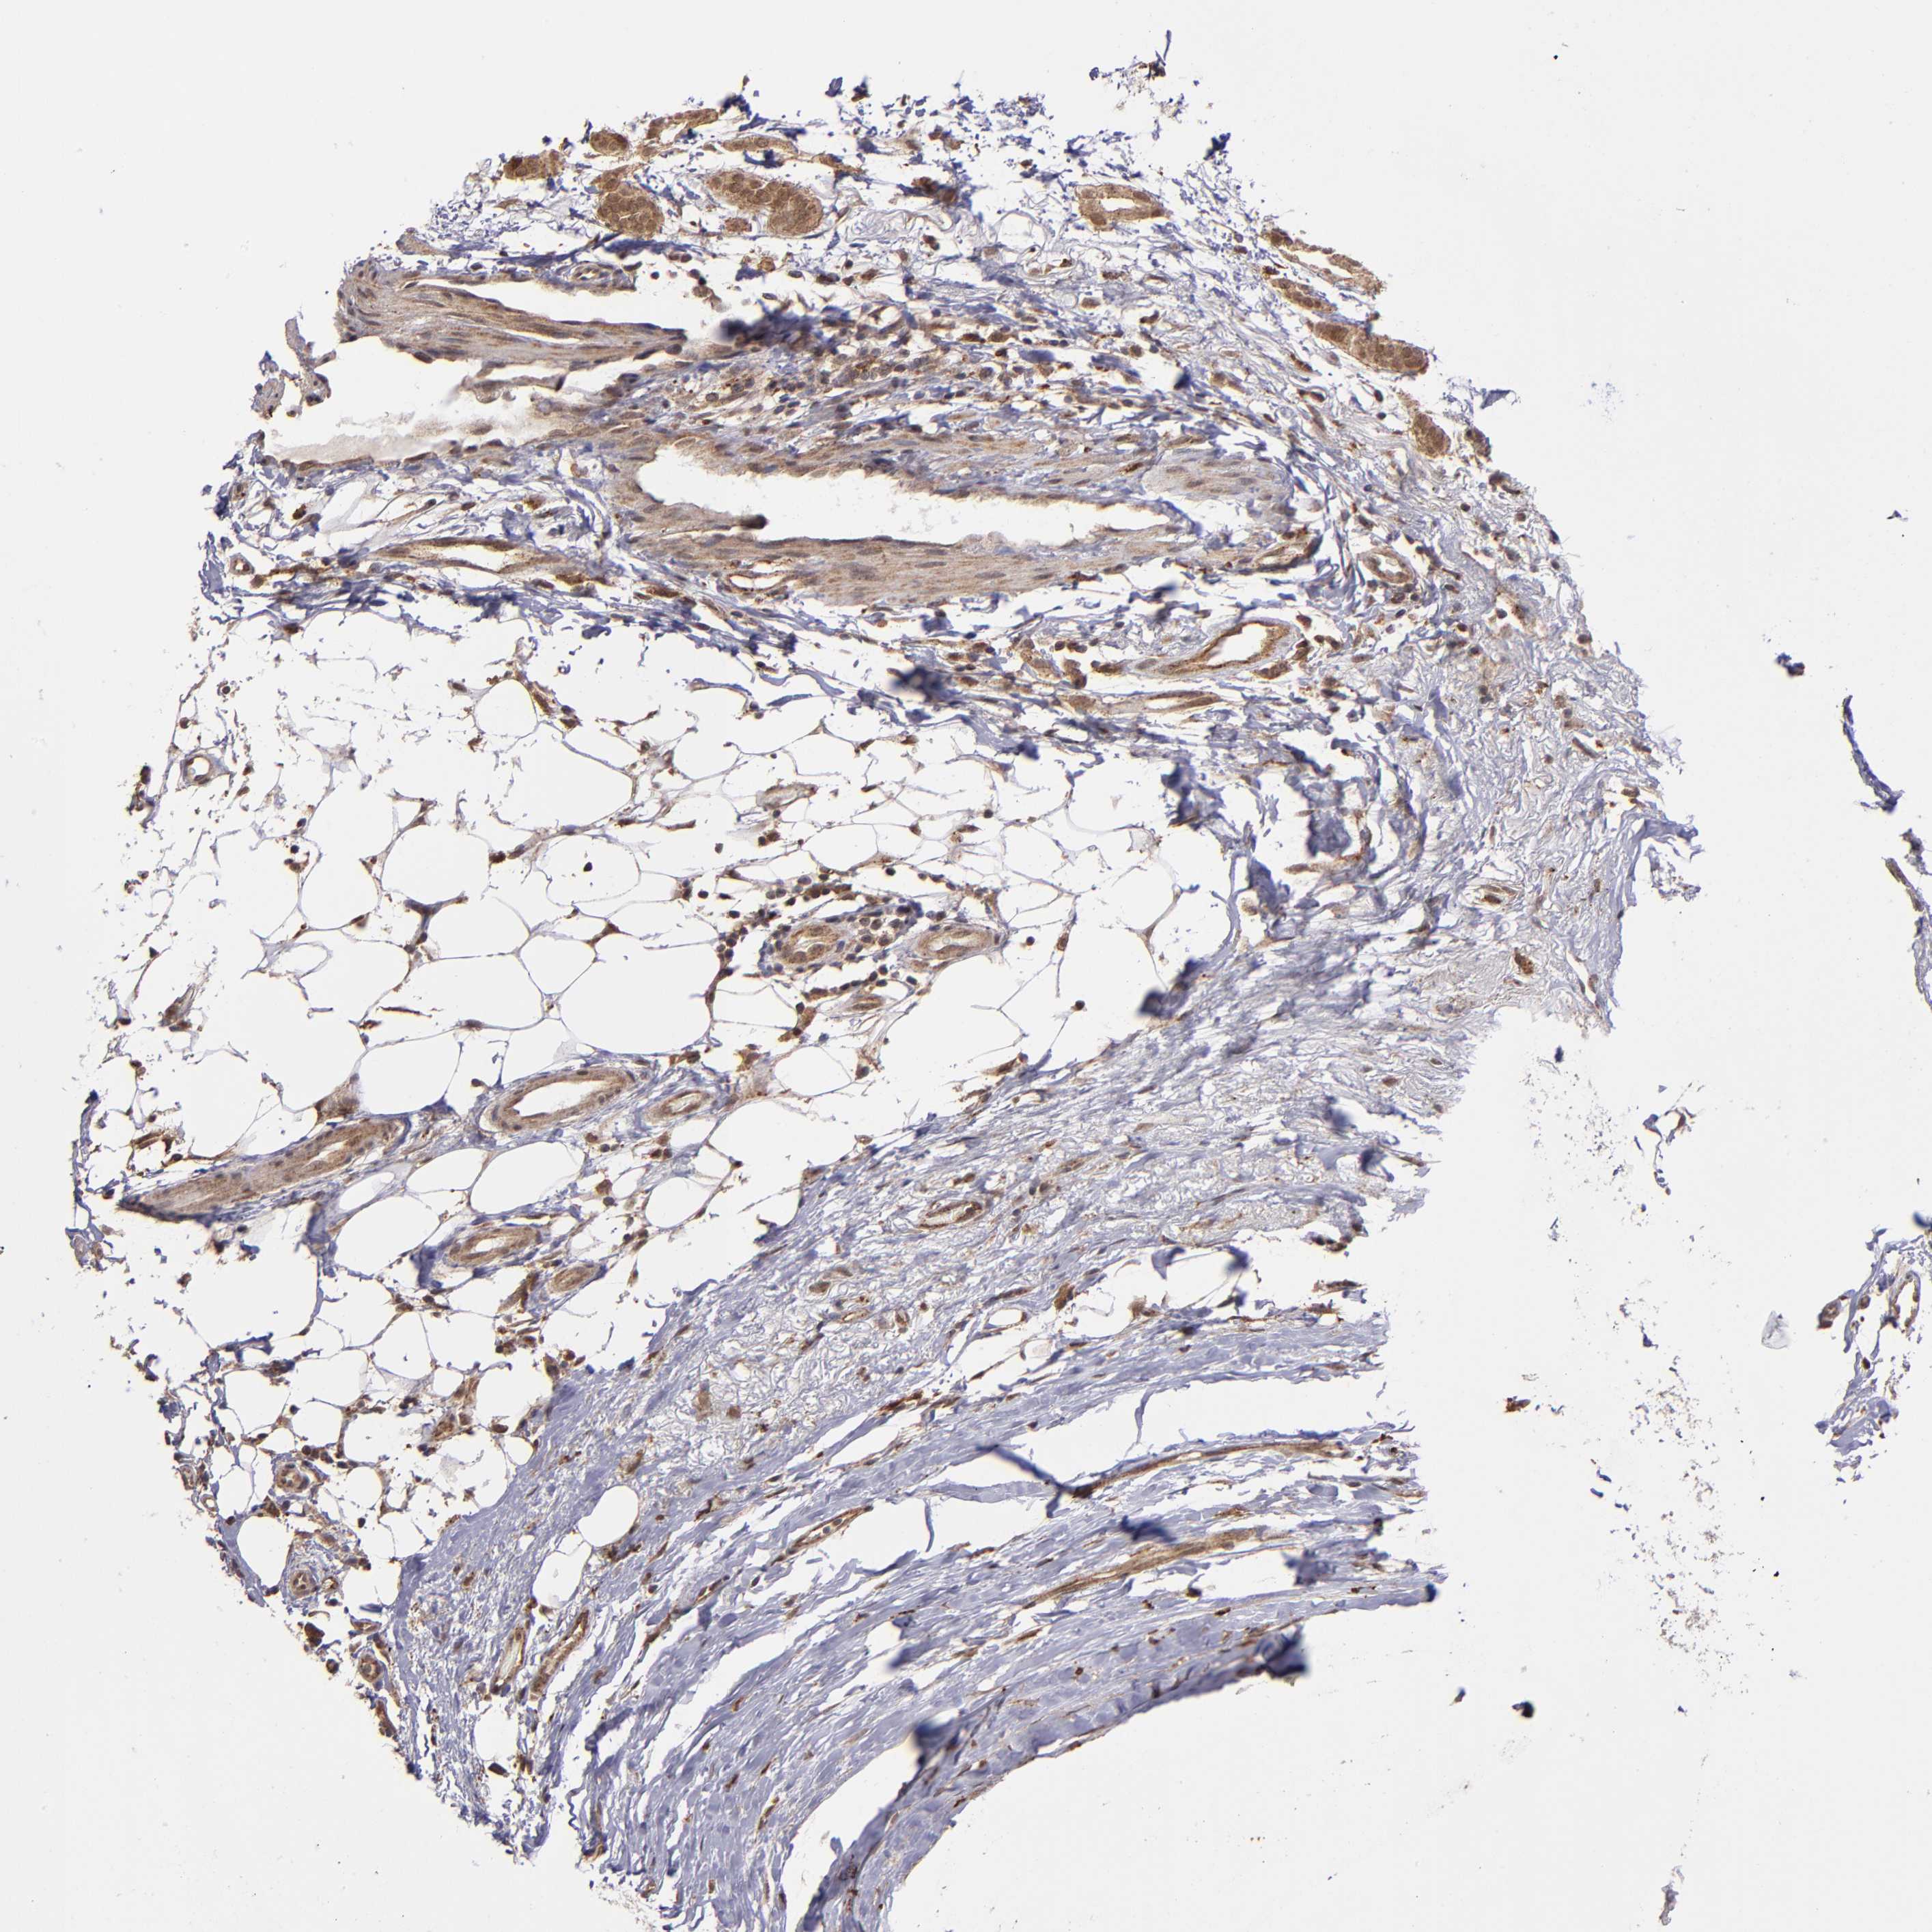

BRCA TCGA BRCA VALIDATION PROTEIN EXPRESSION